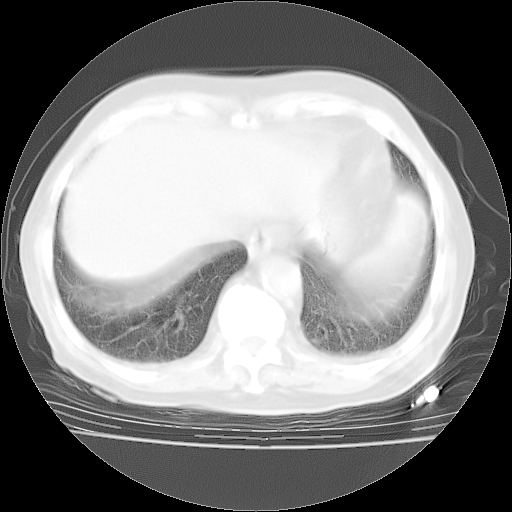

今天部分检查

轻微咳嗽,无痰,(体温正常时)R20次/分,P75次/分,双肺底、腋下可闻及少量捻发音。下肢轻度浮肿。

血常规:白细胞9.11×109/L,N0.92,L5.64,血小板39.2×109/L,HB148g/L,ESR2mm/H。

尿常规:潜血+

血生化:总蛋白69.71g/L,白蛋白38.40g/L,球蛋白31.31g/L,CRP27.9mg/L,尿素氮11.98mmol/L,肌酐106μmol/L,乳酸脱氢酶1099 U/L,肌酸激酶108U/L,CK-MB 61U/L。

腹部B超:胆囊壁增厚,肝、胆、胰、脾、肾无异常,肠系膜淋巴结、腹膜后淋巴结无增大。

ECG:右心室增大

心脏超声检查:无右心室增大。

增加治疗:异烟肼、利福平、乙胺丁醇,静滴左氧氟沙星、参麦注射液。甲强龙从80mg暂减为40mg。

强的松3月1日改为10mg qd,4月1日改为10mg qod。3月份以前的减量过程和环磷酰胺疗程需等明天查看记录(我岳父自己做的记录在他家里)。